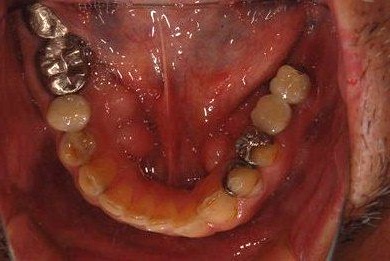

| 性別/年齢 | 男性 / 53歳 | ||||||||||||||||||||||||||||||||

| 主訴 | 左下奥歯2本のインプラント治療を希望。 | ||||||||||||||||||||||||||||||||

| 治療方針 | 左下欠損部分をインプラント治療にて機能的・審美的回復を行う。 | ||||||||||||||||||||||||||||||||

| 治療内容 | インプラント2本、ハイブリッドセラミッククラウン2本 | ||||||||||||||||||||||||||||||||

| 総治療費 | 399,000円 | ||||||||||||||||||||||||||||||||

| 治療期間 | 9ヶ月 |